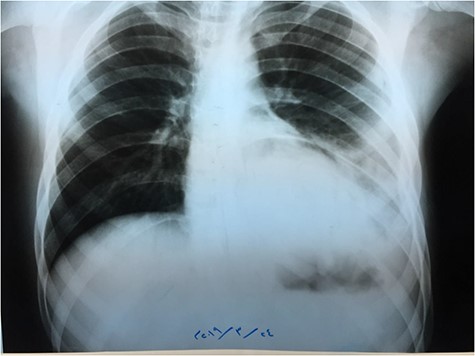

An X-ray image (Fig. 4) was done 24 h after the operation, and it showed good improvement.